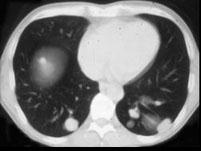

问题 女,38岁,低热乏力并消瘦2个月余,CT如图所示,下列说法正确的是 ( )

选项 A、肺内多发小结节病灶,考虑为肺转移瘤 B、肺内多发小结节病灶,考虑为肺结核 C、左侧肾上腺区巨大的占位性病灶考虑为嗜铬细胞瘤 D、左侧肾上腺区巨大的占位性病灶考虑为肾上腺腺瘤 E、左侧肾上腺区巨大的占位性病灶考虑为肾上腺癌

答案 AE